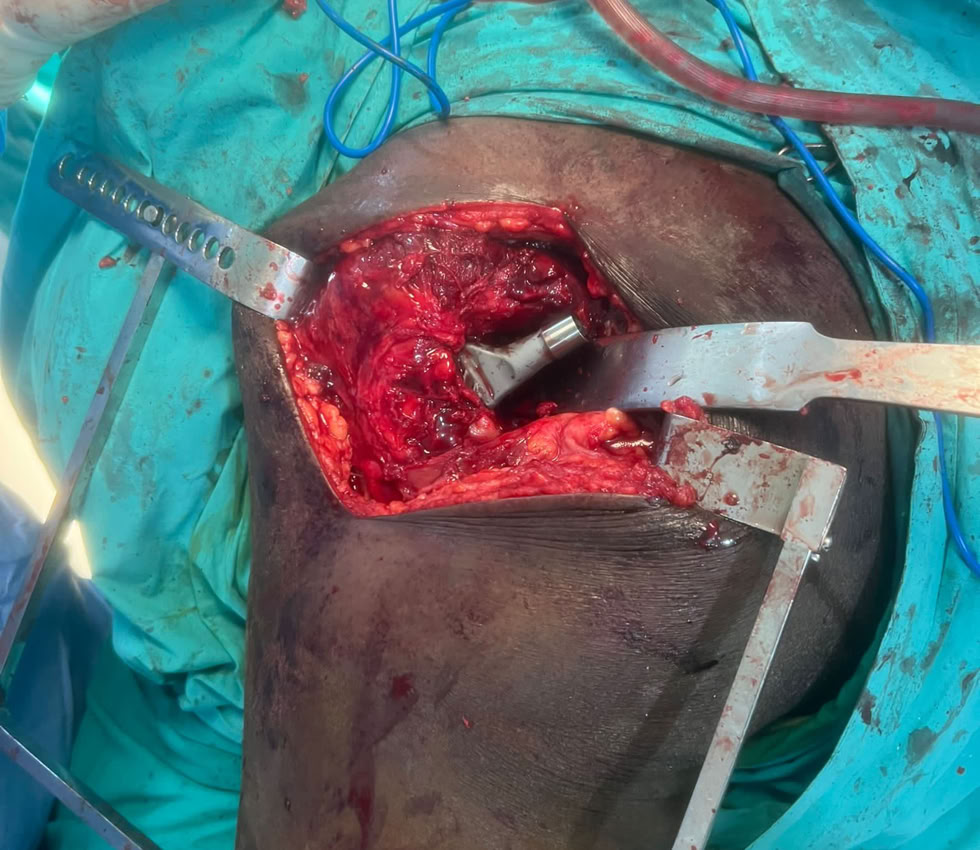

Nada mas llegar, fractura de fémur y tibia abiertas . Dos magníficas traumatólogas, una enfermera excepcional y una anestesista fuera de serie, resolvieron la urgencia.

Gran carga de trabajo por las múltiples fracturas que hemos atendido, pero también hemos tenido tiempo de hacer una Prótesis Total de Cadera,  a un paciente de 71 años con una Necrosis Avascular de Cabeza Femoral . Le hemos mejorado la calidad de vida, ya que estaba prácticamente inválido y aquí podemos ver como se maneja caminando a las 48 h de la intervención